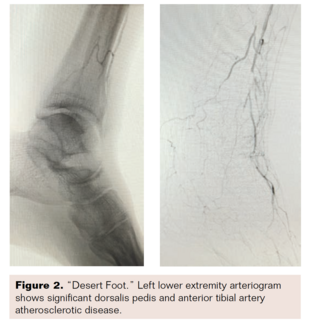

I this case, rather than opting for amputation in a patient with CLI not amenable to open bypass surgery or endovascular therapy, a novel open surgical approach was used to revascularize the pedal arteries.